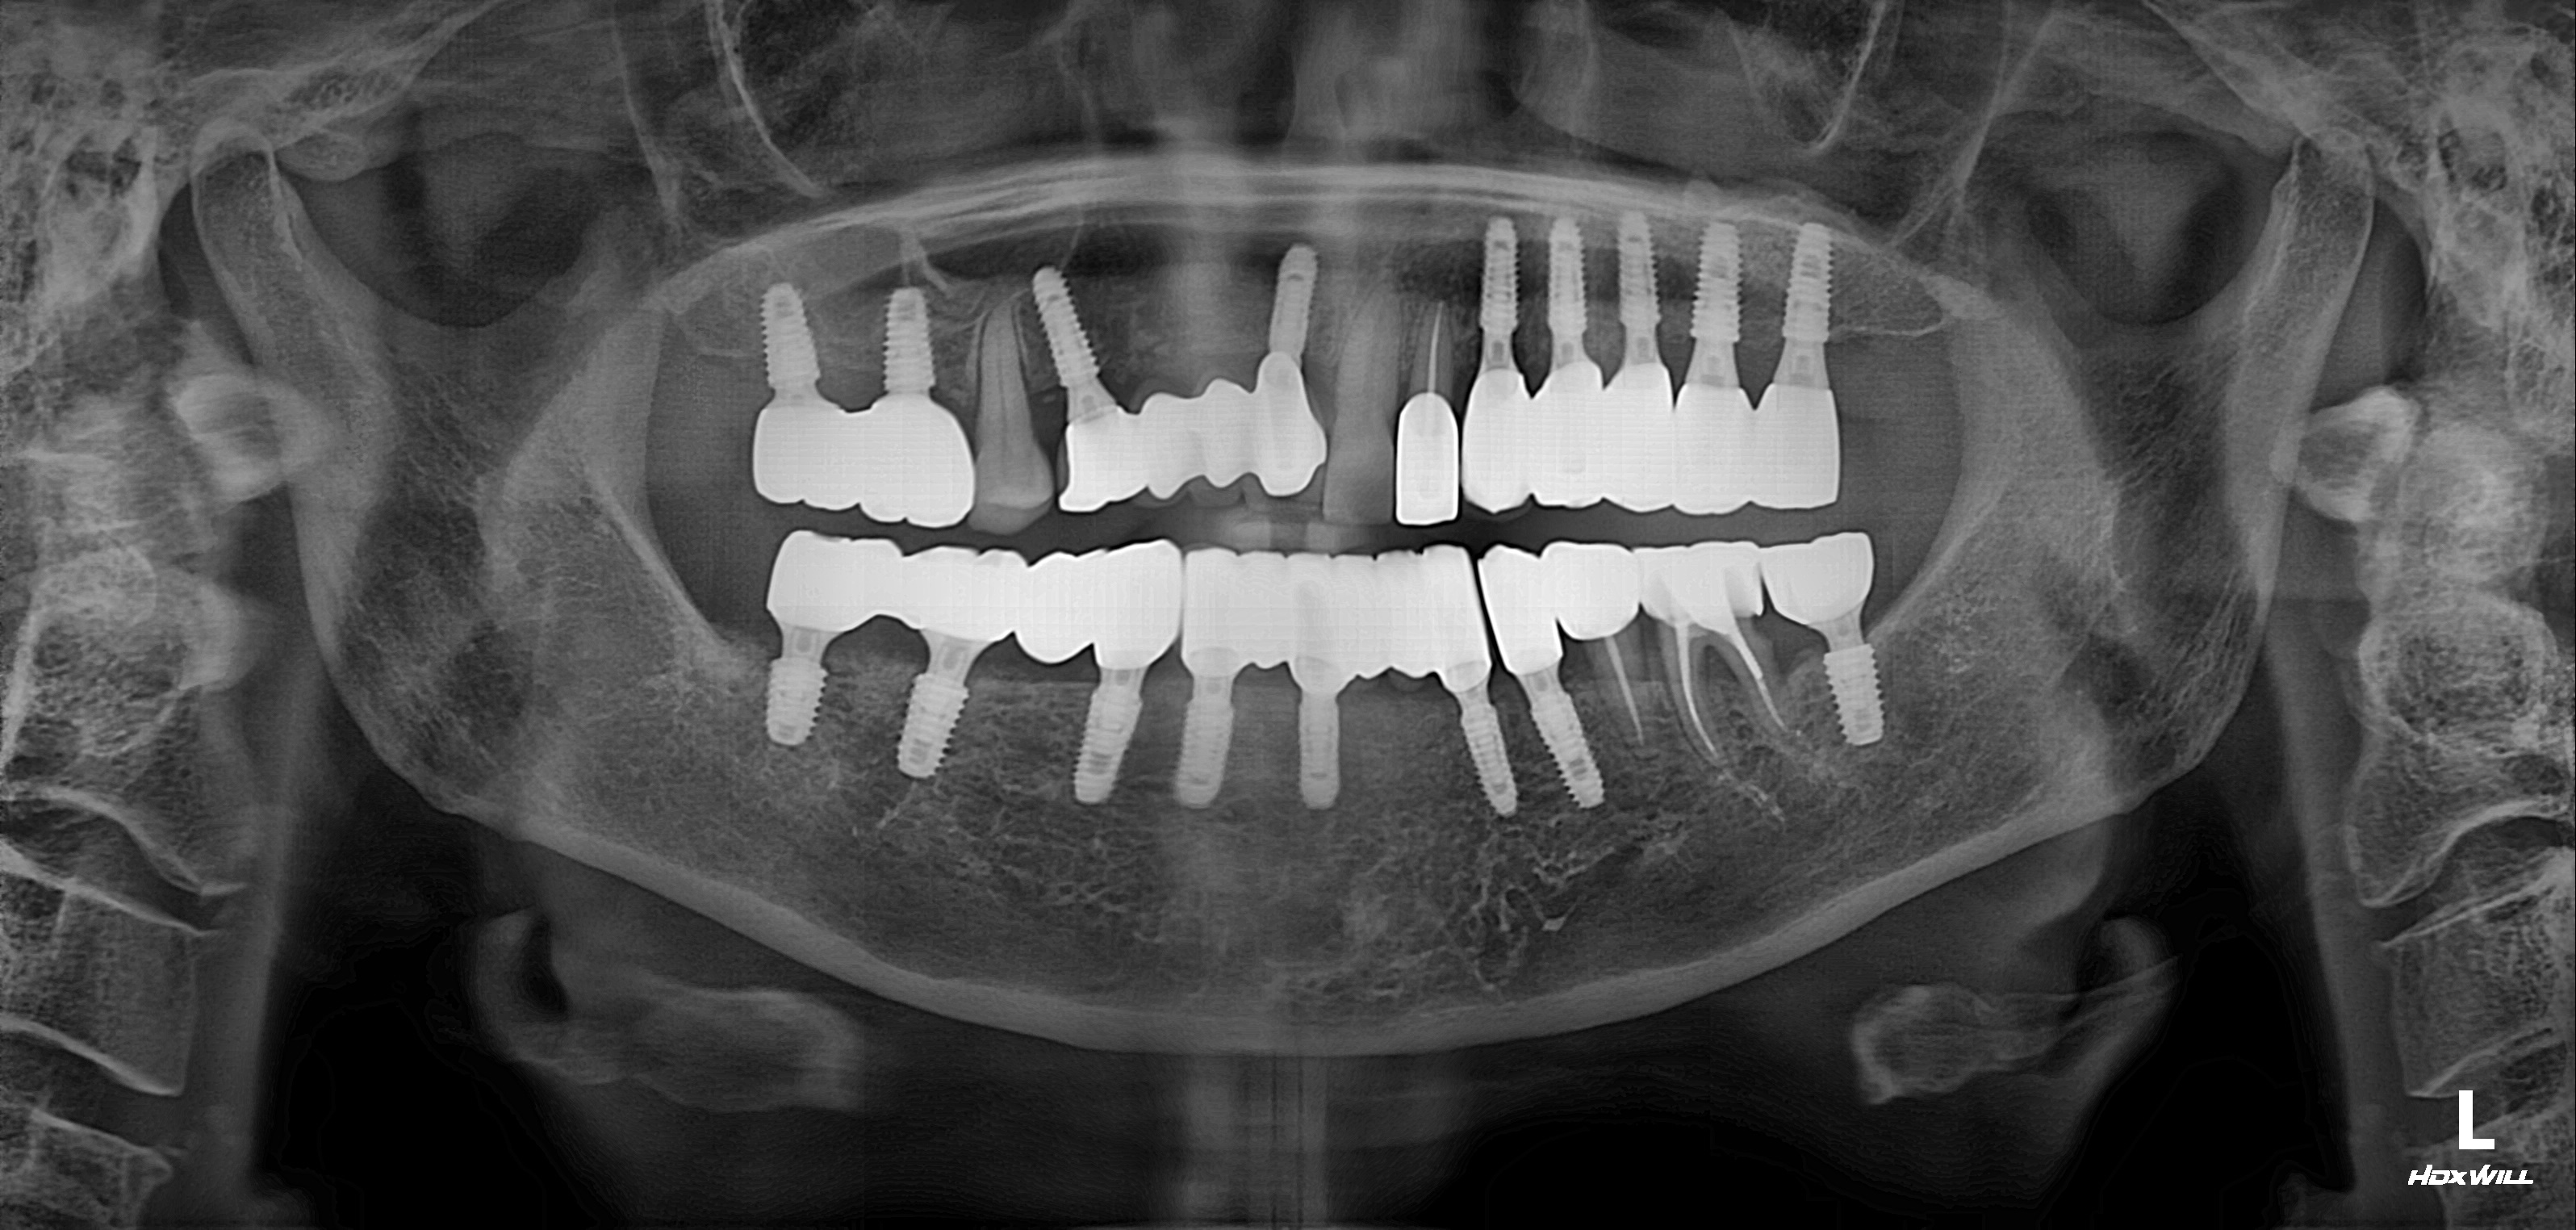

하악 전체+상악 구치부 임플란트 식립사례